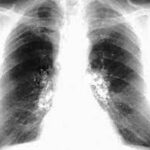

La intoxicación por bloqueadores beta-adrenérgicos es un fenómeno clínico complejo que se asocia a la administración excesiva o inadecuada de fármacos que actúan sobre los receptores beta-adrenérgicos del sistema nervioso…